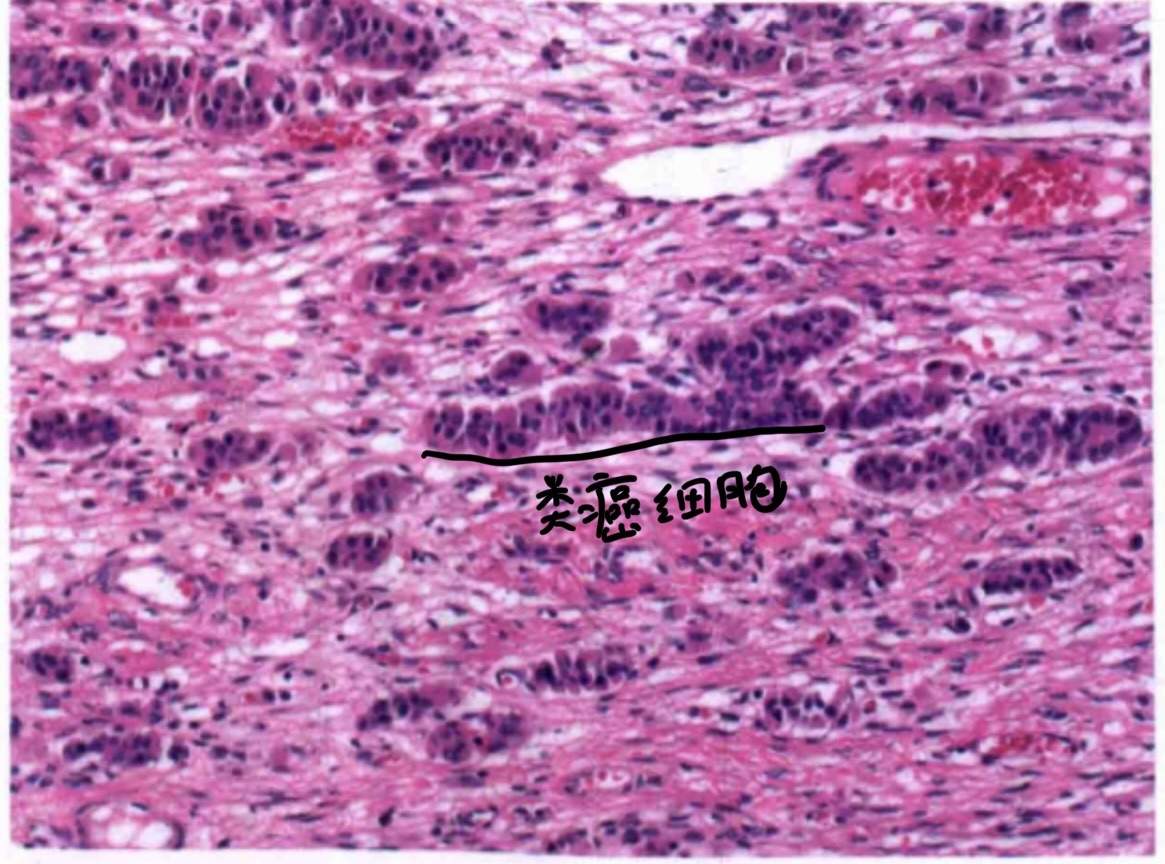

2)印戒细胞样间质瘤

它的关键词是:印戒样细胞不表达粘液不表达脂质,如图:

电镜观察标明,这里的印戒样细胞可能是基质水肿造成,也可能是线粒体肿胀造成。需要与Krukenberg瘤(黏液染色阳性+硬化性间质)鉴别。